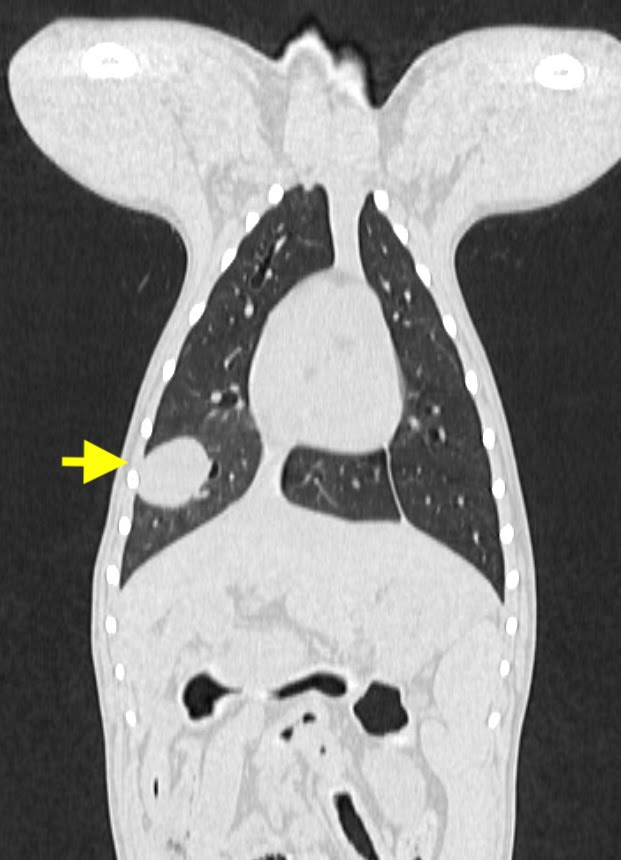

この症例は無症状でしたが、健康診断のレントゲン検査で、肺に単発性の腫瘍が発見されました。

腫瘍の発生部位や転移の有無を精査するため、他院でCT検査を行なってもらい、外科的切除が適応と判断しました。